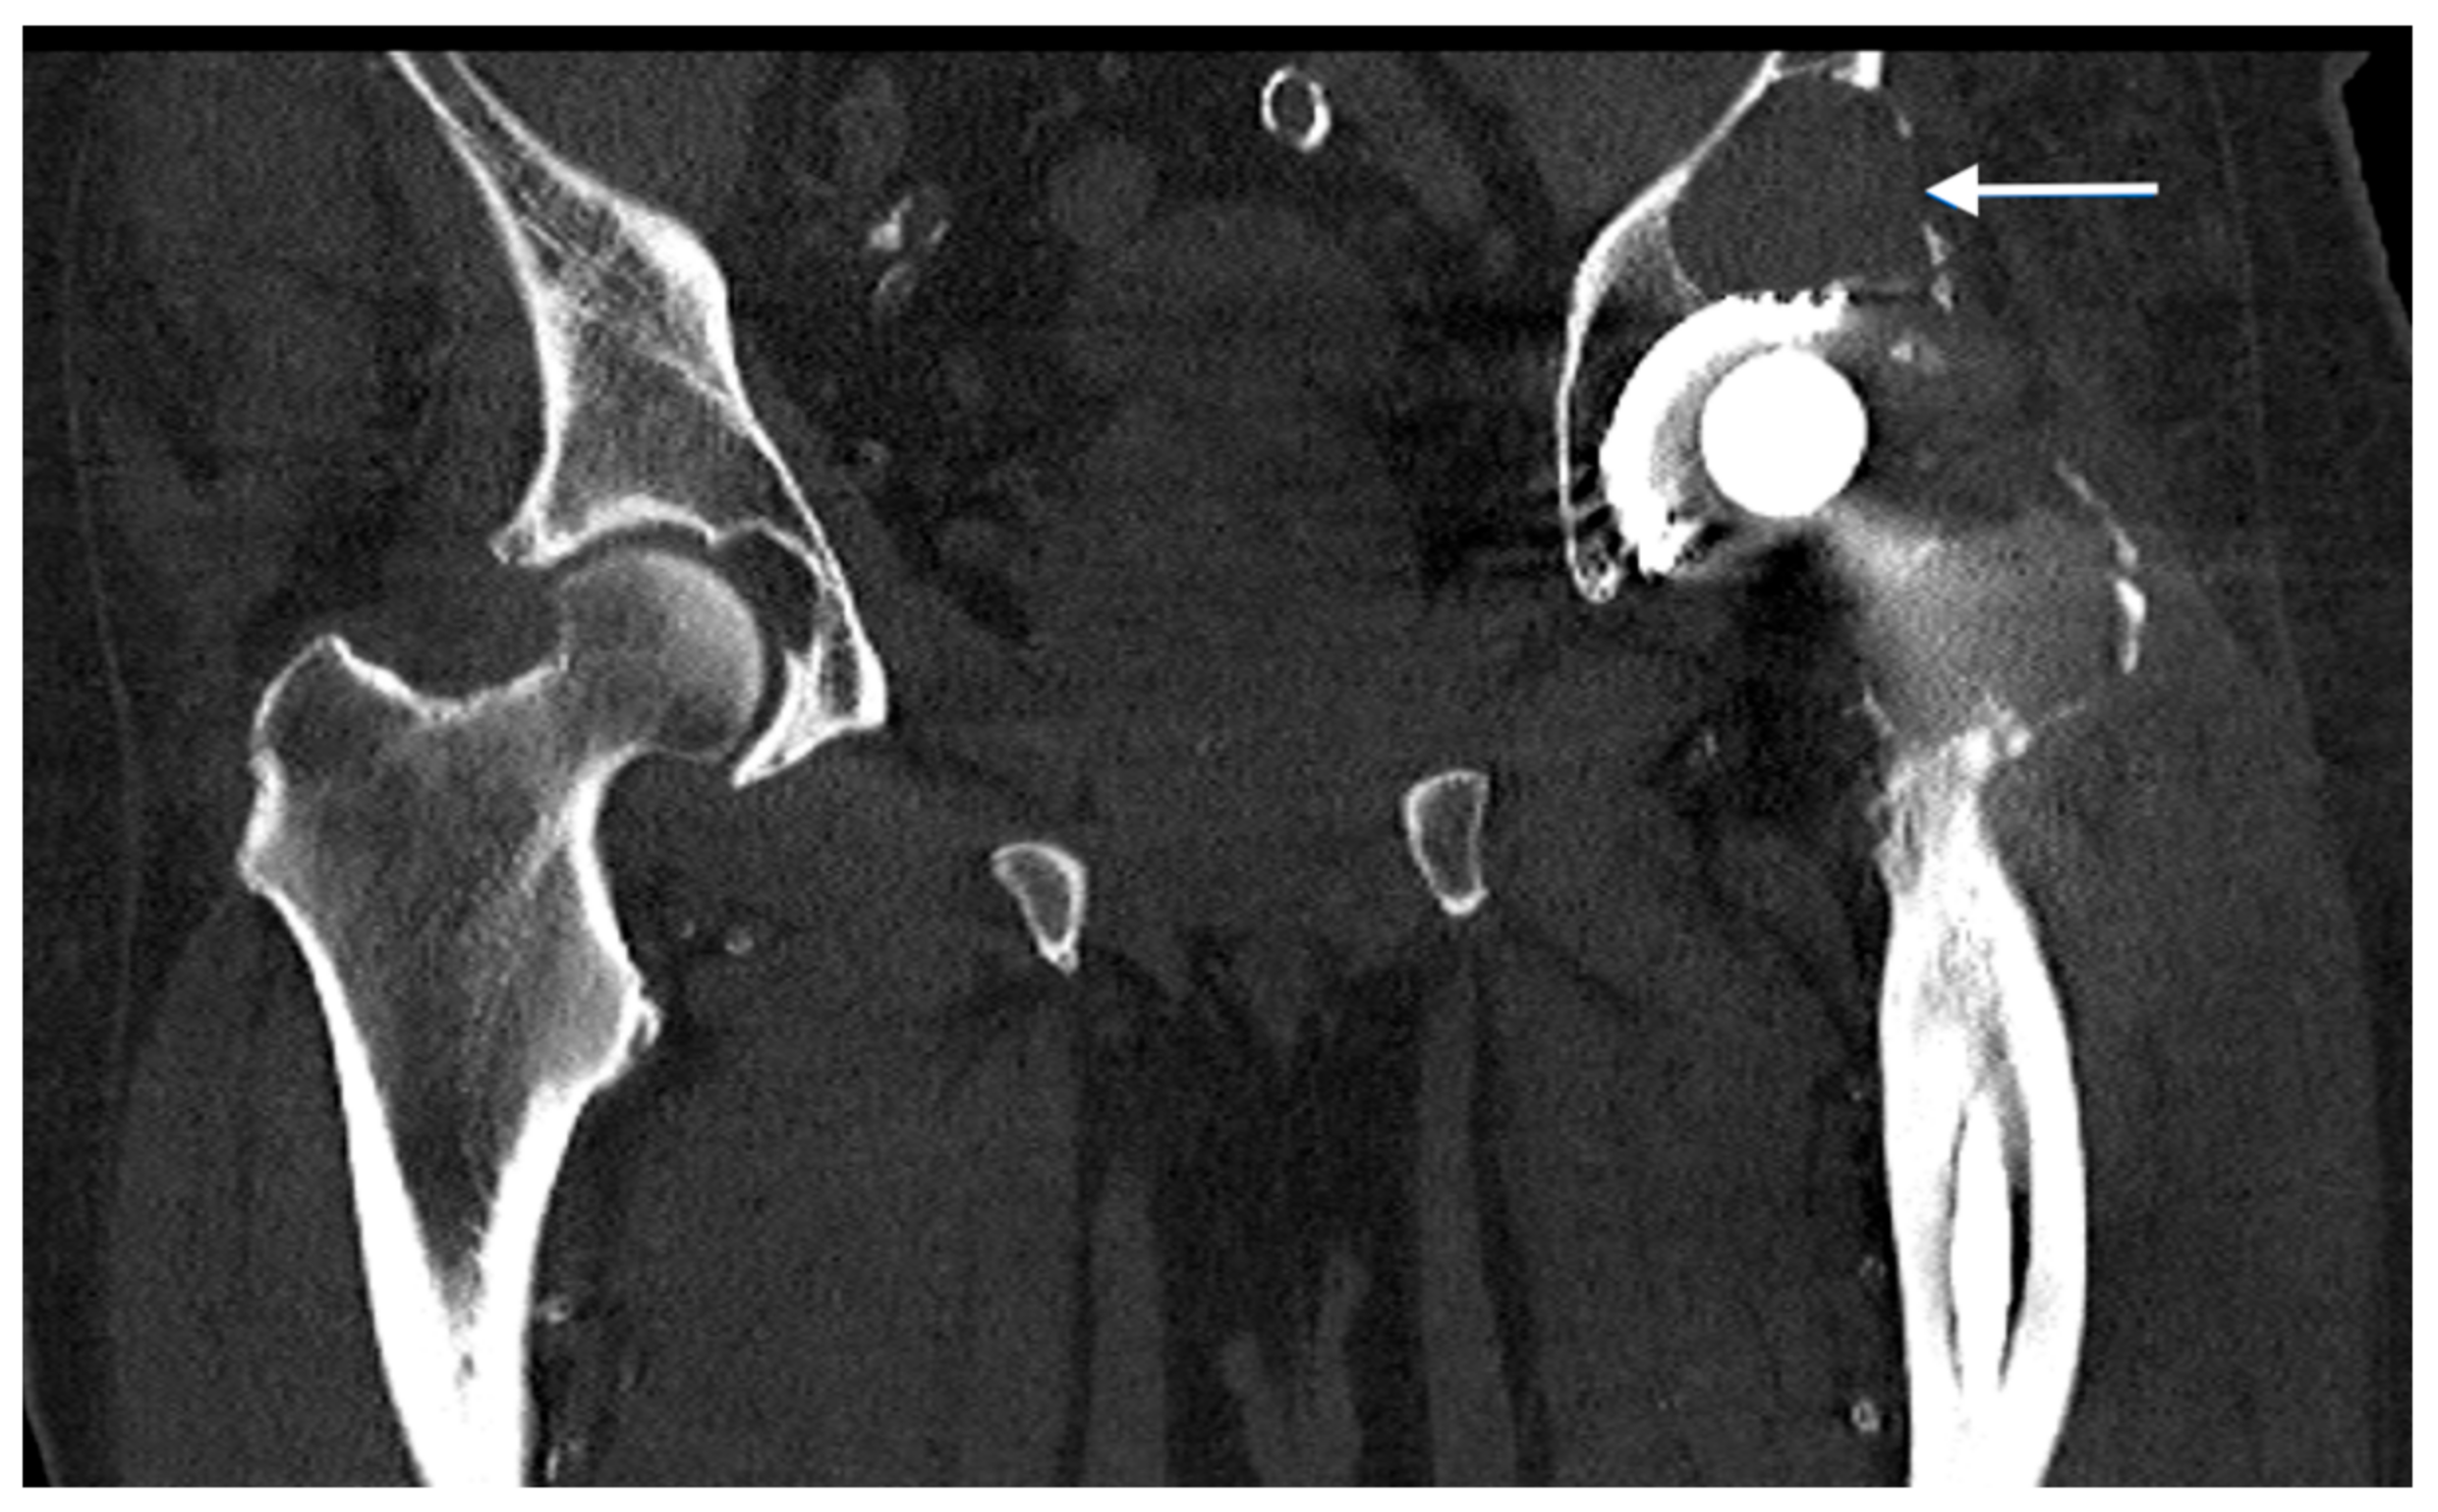

2.1. Preoperative Imaging

2.2. Digital Templating